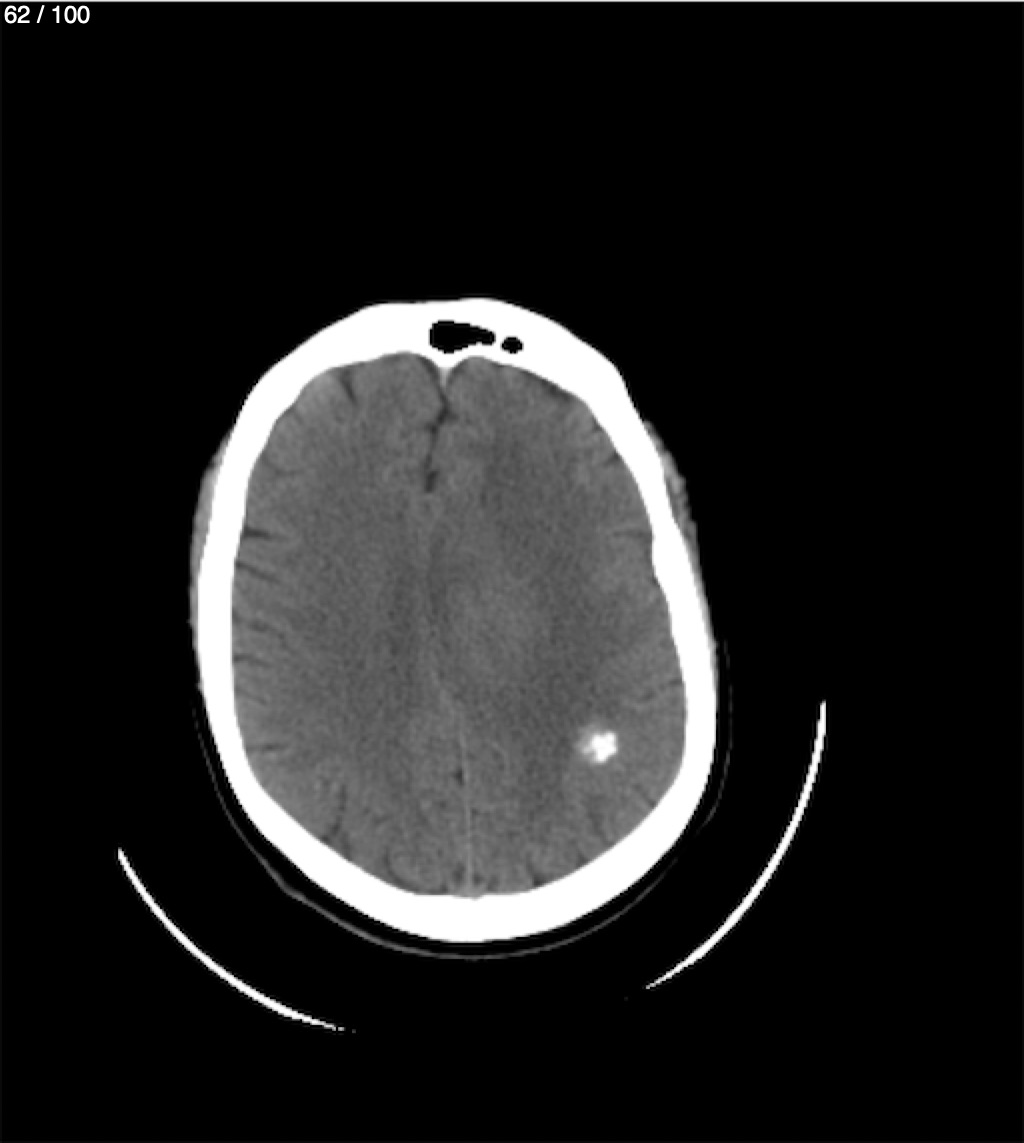

Valentin Perez Gomez 69A - T.C Craneo